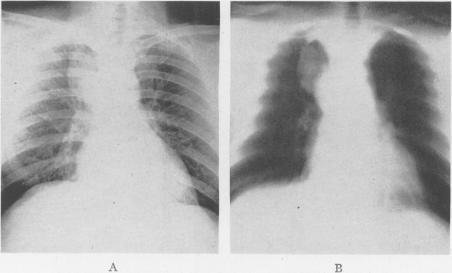

Bronchiogenic Cysts of the Mediastinum.

Ann Surg. 1948 Mar;127(3):476-502. doi: 10.1097/00000658-194803000-00010.